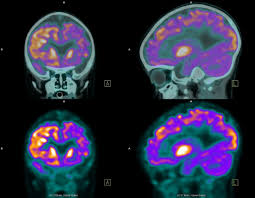

또 부수적으로 뇌 부분의 PET 영상으로 분석해 뇌졸중, 알츠하이머 치매도 조기 진단할 수 있다고 한다. 검사도 간단해서 정맥 주사를 맞고 1시간대기 후에 20분 정도 누운 상태로 촬영한다.